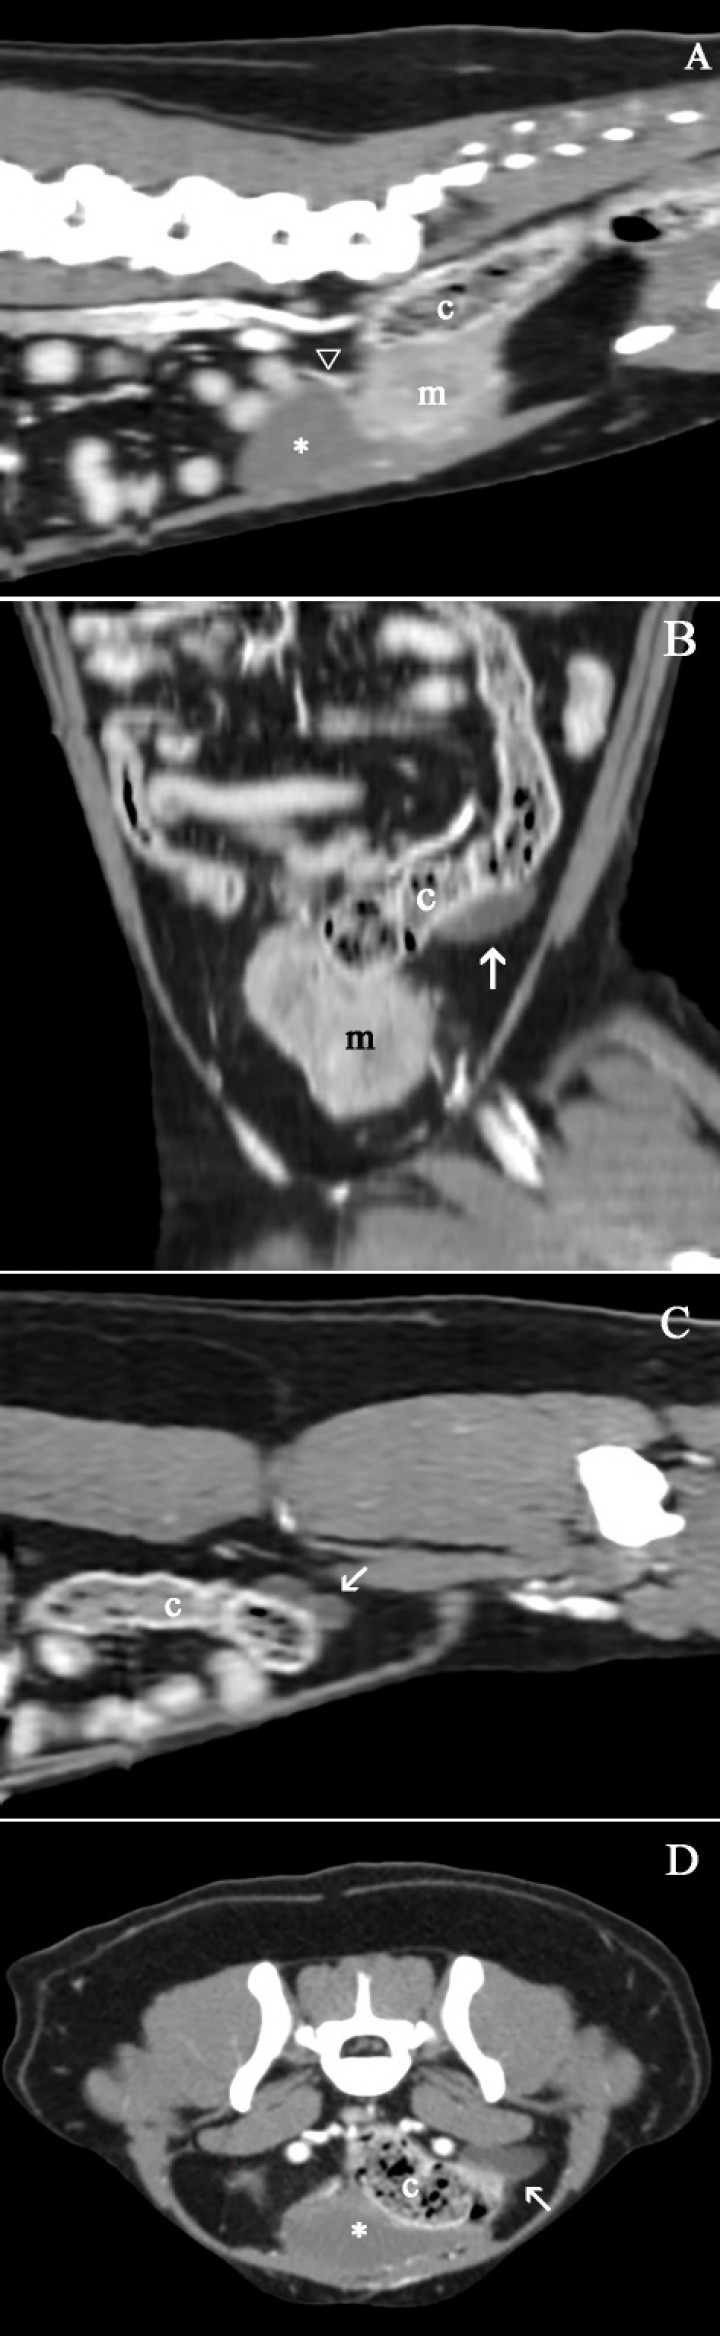

El estudio de TC se evaluó en ventana de tejido blando y hueso, visualizándose una masa caudal y dorsal a la vejiga de la orina, de forma ovalada, bordes bien definidos de atenuación tejido blando (60 UH) y con medidas aproximadas de 3,10 cm (altura) x 4,32 cm (anchura) x 4,10 cm (longitud). Tras la administración del contraste la masa presentaba una captación de contraste levemente heterogénea (150 UH) inmediatamente y a los 5 minutos (120 UH) (Fig. 3A). Además, se observó hidronefrosis e hidrouréter izquierdo, este último con un trayecto tortuoso cuya visualización se interrumpía a nivel del abdomen caudal, adyacente al colon y sin poder observar su inserción en la vejiga (Figs. 3B, C y D). El uréter derecho se visualizó con un diámetro normal y relleno de contraste, bordeando la masa en dirección dorsal y lateral e introduciéndose en el interior de esta (Fig. 3A). El diagnóstico fue el mismo que se realizó en la ecografía, observándose, además, la adherencia del uréter derecho a la masa.

<p>mágenes de tomografía computarizada en ventana de tejido blando y post-contraste inmediato: (<strong>A</strong>) Corte sagital. (<strong>B</strong>) Corte dorsal oblicuo. (<strong>C</strong>) Corte parasagital. (<strong>D</strong>) Corte transversal. Se visualiza la masa (m) caudal a la vejiga de la orina (asterisco) y ventral al colon descendente (c) con una captación de contraste ligeramente heterogénea. El uréter izquierdo se visualiza dilatado, con un trayecto tortuoso (flechas blancas) e íntimamente relacionado al colon descendente (c). El uréter derecho se visualiza íntimamente relacionado con la masa en su inserción en la vejiga de la orina, presentando un tamaño normal (cabeza de flecha blanca).</p>

mágenes de tomografía computarizada en ventana de tejido blando y post-contraste inmediato: (A) Corte sagital. (B) Corte dorsal oblicuo. (C) Corte parasagital. (D) Corte transversal. Se visualiza la masa (m) caudal a la vejiga de la orina (asterisco) y ventral al colon descendente (c) con una captación de contraste ligeramente heterogénea. El uréter izquierdo se visualiza dilatado, con un trayecto tortuoso (flechas blancas) e íntimamente relacionado al colon descendente (c). El uréter derecho se visualiza íntimamente relacionado con la masa en su inserción en la vejiga de la orina, presentando un tamaño normal (cabeza de flecha blanca).

Las técnicas de imagen avanzadas como la TC nos pueden ayudar a elaborar un plan quirúrgico adecuado debido a que eliminamos la superposición de estructuras que ocurre en las radiografías y los artefactos ecográficos, que pueden aparecer cuando la masa se localiza en abdomen caudal y se extiende por el canal pélvico. Además, se obtiene una visión más amplia y en varios planos de la masa, así como la relación de esta con otras estructuras.[ Rozear L and Tidwell AS: Evaluation of the ureter and ureterovesicular junction using helical computed tomographic excretory urography in healthy dogs. Vet Radiol ultrasound 2003; 44(2): 155-164. [pubMed] ] En este caso, la masa se observó caudal y dorsal a la vejiga de la orina, de morfología ovalada y bien definida, de atenuación tejido blando y con una captación de contraste ligeramente heterogénea. Además, debido a que el contraste administrado por vía endovenosa se excreta por los riñones,[ Rozear L and Tidwell AS: Evaluation of the ureter and ureterovesicular junction using helical computed tomographic excretory urography in healthy dogs. Vet Radiol ultrasound 2003; 44(2): 155-164. [pubMed] ] nos permitió visualizar el trayecto de ambos uréteres y observar así el uréter izquierdo dilatado y tortuoso, mientras que el uréter derecho se encontraba involucrado en la masa y presentaba un diámetro normal.